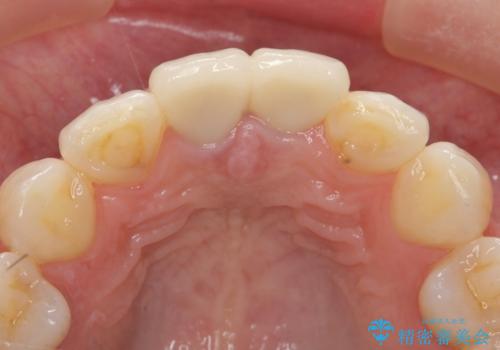

X線写真検査に加え圧痛、打診痛が認められたため、慢性根尖性歯周炎と診断し、根管治療から行うセラミック治療を計画します。

- 26.2万円(仮歯・ファイバーコア・ジルコニアクラウン×2)費用は治療当時の料金となります

今回は根尖性歯周炎に対する根管治療を行ったことで症状は改善し、快適に食事ができる状態へと改善しました。